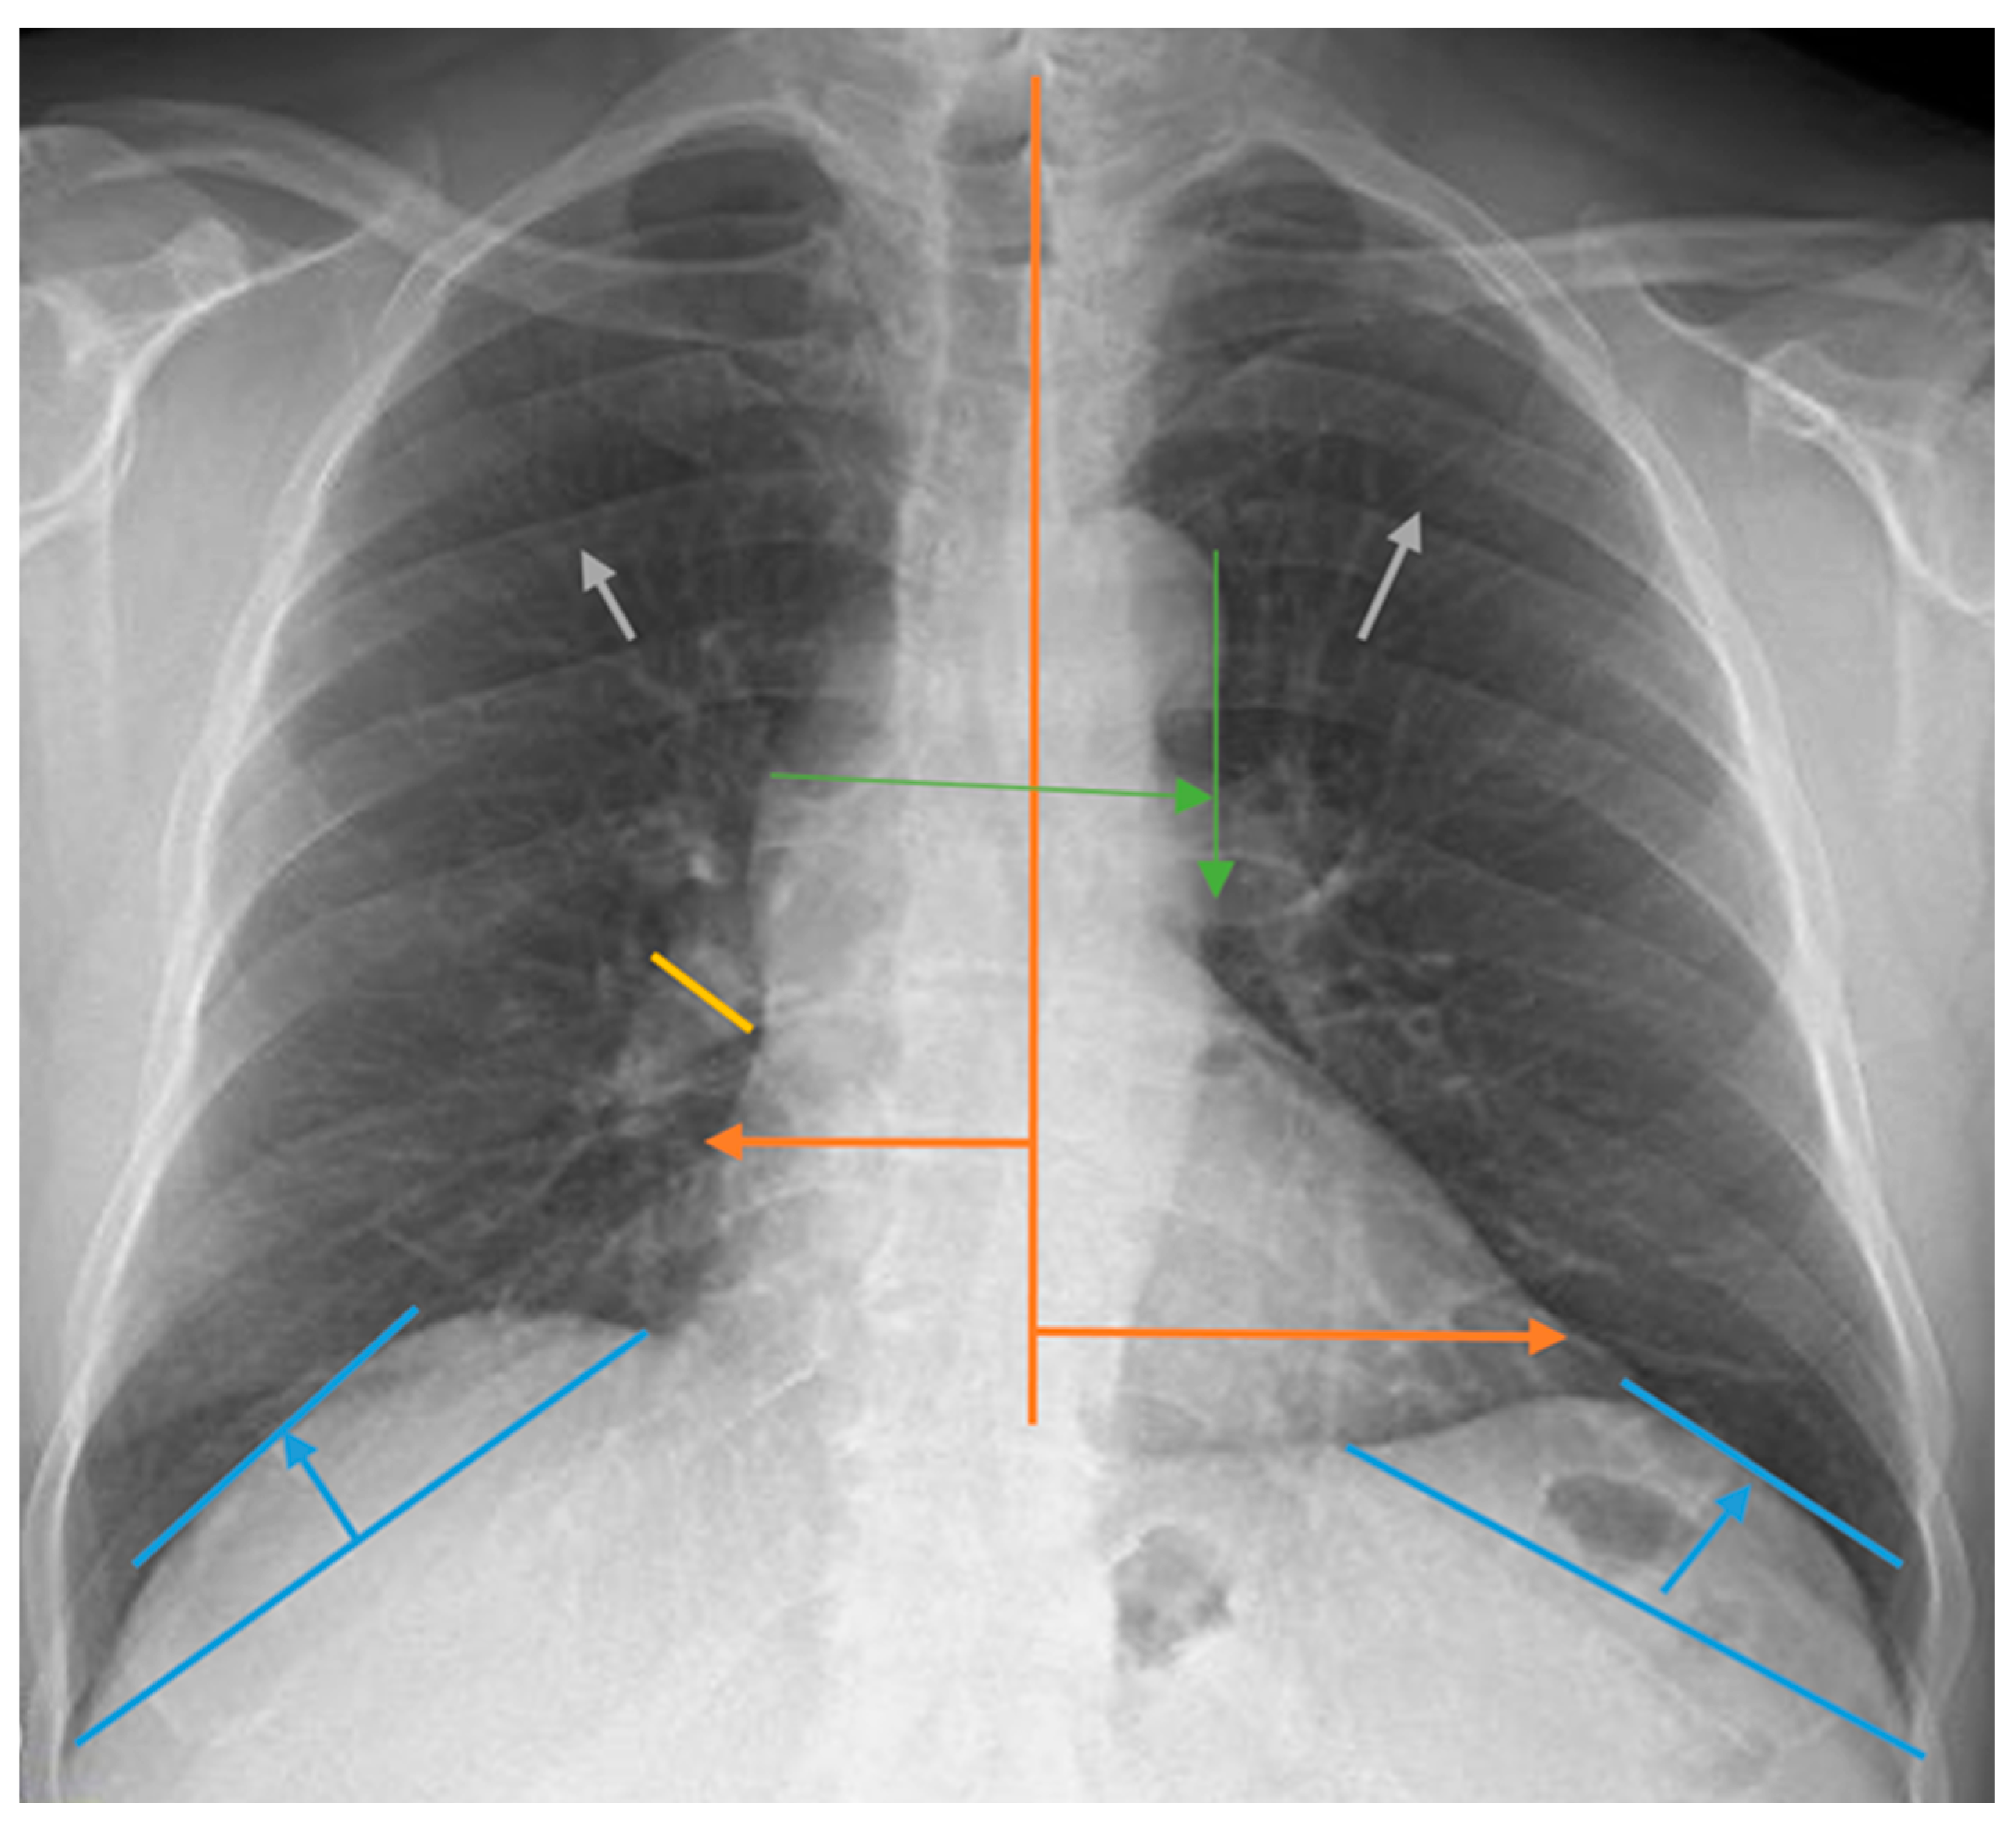

Measurements for the evaluation of chest radiographs, CTI, heart width, pulmonary vascular pedicle width, pulmonary artery diameter, pulmonary redistribution, diaphragm height, and diaphragm width are shown in Figure 1. CTI is the ratio calculated by dividing the heart’s widest diameter by the chest cavity’s widest internal diameter. For this measurement, 0.42 and 0.50 were considered normal values. Above 0.50 was defined as cardiomegaly [19]. PVPW is used to detect heart failure and volume overload. It was measured as the distance from the outer edge of the aortic arch (just below the upper border of the left main pulmonary artery) to the outermost border of the right main pulmonary artery. PVPW < 70 mm was considered normal [15]. Right pulmonary artery diameter is used to detect pulmonary hypertension, right heart failure, and volume overload. The right pulmonary artery was measured closest to the midline of the pulmonary hilus. Right pulmonary artery diameter < 17 mm was considered normal [20]. Normal diaphragmatic height was generally considered 1.5–2.5 cm on the right and 1.0–2.0 cm on the left. This measurement is used to assess the functional status of the lungs and diaphragm. Pulmonary redistribution is the redistribution of blood flow from the lower lobes to the upper lobes of the lungs, where it is usually more concentrated. Its impairment becomes evident in diseases such as heart failure, fluid overload, and pulmonary hypertension. Other lung findings evaluated are pleural fluid, pleural thickness, alveolar infiltration, aortic calcification, and atelectasis. However, these parameters were not measured. Their presence or absence on chest radiography was taken into consideration. The acceptance criteria for radiologic status were defined as follows: improvement was indicated by a reduction in the diameter of the CTI and PVPW, a reduction in pleural fluid, and an improvement in parenchymal findings such as interstitial and alveolar changes. Stability was defined as no change in any of these parameters, while deterioration was characterized by a lack of improvement in these areas. Similarly, the criteria for clinical status in dialysis patients included improved symptoms such as fatigue and muscle cramps, enhanced laboratory results including calcium, phosphorus, serum creatinine, and urea levels, and better blood gas results. Stability was noted when there was no change in these parameters, and deterioration was identified by the absence of improvements.

Figure 1.

Chest radiograph measurements. Orange line: cardiothoracic index; green line: pulmonary vascular pedicle width; yellow line: right pulmonary artery diameter; blue line: diaphragmatic height; gray arrows: pulmonary redistribution.

How the chest radiograph measurement calculations used in this study were performed is shown in Figure 1.